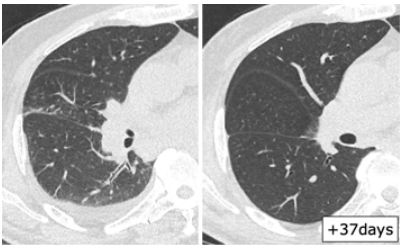

日本一项研究总结了血液系统疾病和造血干细胞移植患者RSV感染的影像学表现,其中一例63岁T淋巴细胞瘤患者感染RSV后症状持续10天,右肺下叶支气管处支气管管壁增厚,经过治疗,情况有所改善(图1)。图2为一例75岁T细胞淋巴瘤患者,起病9天,肺上叶可见小叶中心结节影(图2)。23岁急性粒细胞白血病患者早期影像学表现为多叶段沿支气管束分布的磨玻璃影,随着时间的延长以及治疗的开展,病变密度逐渐增加、皱缩及吸收(图3)。图4为一例78岁慢粒患者,羟基脲治疗,起病1天,影像学可见铺路石征,随着时间的延长,逐渐吸收(图4)

图片

图3  23岁急性粒细胞白血病患者感染RSV的影像学表现

图源:Intern Med. 2020;59(2):247-252.